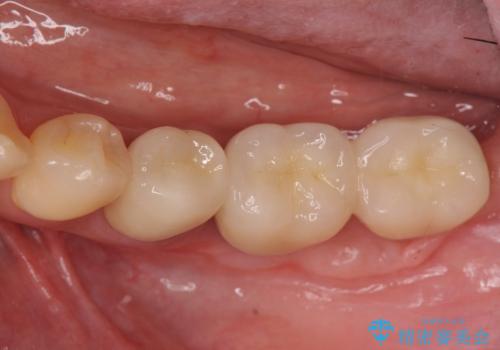

遊離歯肉移植術を併用した、破折歯のインプラント治療

抜歯後、インプラントを用いて咬合機能を回復すると共に周囲に強固な角化歯肉を移植することによりより長期にわたり安定したインプラント周囲環境となるよう治療を計画します。

インプラント周囲の角化歯肉が存在することにより、歯ブラシがしやすくなりインプラントにトラブルが起きる確率を減らしより長期的な予後を望むことができます。